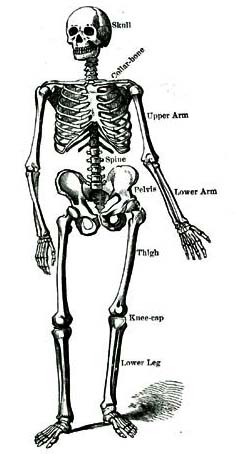

1. Parts of the Body.—What do we call the main part of a tree? The trunk, you say. The main part of the body is also called its trunk. There are two arms and two legs growing out of the human trunk. The branches of a tree we call limbs, and so we speak of the arms and legs as limbs. We sometimes call the arms the upper extremities, and the legs the lower extremities. At the top of the trunk is the head.

2. Names of the Parts.—Now let us look more closely at these different parts. As we speak the name of each part, let each one touch that part of himself which is named. We will begin with the head. The chief parts of the head are the skull and the face. The forehead, the temples, the cheeks, the eyes, the ears, the nose, the mouth, and the chin are parts of the face.

3. The chief parts of the trunk are the chest, the abdomen (ab-do´-men), and the backbone. The head is joined to the trunk by the neck.

4. Each arm has a shoulder, upper-arm, fore-[Pg 6]arm, wrist, and hand. The fingers are a part of the hand.

5. Each leg has a hip, thigh, lower leg, ankle, and foot. The toes are a part of the foot.

1. The body has a head and trunk, two arms, and two legs.

2. The parts of the head are the skull and face. The forehead, temples, cheeks, eyes, ears, nose, mouth and chin are parts of the face.

3. The parts of the trunk are, the chest, abdomen, and backbone. The neck joins the head and trunk.

4. Each arm has a shoulder, upper-arm, fore-arm, wrist, and hand. The fingers belong to the hand.

5. Each leg has a hip, thigh, lower leg, ankle, and foot. The toes belong to the foot.

3. The Bones.—If you take hold of your arm, it seems soft on the outside; and if you press upon it, you will feel something hard inside. The soft part is called flesh. The hard part is called bone. If you wish, you can easily get one of the bones of an animal at the butcher's shop, or you may find one in the fields.

4. The Skeleton.—All the bones of an animal, when placed properly together, have nearly the shape of the body, and are called the skeleton (skel´-e-ton). The skeleton forms the framework of the body, just as the heavy timbers of a house form its framework. It supports all the parts.

5. The Skull.—The bony part of the head is called the skull. In the skull is a hollow place or chamber. You know that a rich man often has a strong room or box in his fine house, in which to keep his gold and other valuable things. The chamber in the skull is the strong-room of the body. It has strong, tough walls of bone, and contains the brain. The brain is the most important, and also the most tender and delicate organ in the whole body. This is why it is so carefully guarded from injury.

[Pg 9]6. The Backbone.—The framework of the back is called the backbone. This is not a single bone, but a row of bones arranged one above another. Each bone has a hole through it, about as large as one of your fingers. A large branch from the brain, called the spinal cord, runs down through the middle of the backbone, so that the separate bones look as if they were strung on the spinal cord, like beads on a string.

7. The Trunk.—The trunk of the body, like the skull, is hollow. Its walls are formed partly by the backbone and the ribs and partly by flesh. A fleshy wall divides the hollow of the trunk into two parts, an upper chamber called the chest, and a lower called the abdomen.

8. The Lungs and Heart.—The chest contains a pair of organs called the lungs, with which we breathe. It also contains something which we can feel beating at the left side. This is the heart. The heart lies between the two lungs, and a little to the left side.

9. The Stomach and Liver.—In the abdomen are some very wonderful organs that do different kinds of work for the body. Among them are the stomach, the bowels, and the liver. There are, also, other organs whose names we shall learn when we come to study them.

1. The body has a framework, called the skeleton.

2. The skeleton is made up of many different parts, each of which is called a bone.

3. The bones are covered by the flesh.

4. The bones of the head form the skull, which is hollow and contains the brain.

5. A row of bones arranged in the back, one above another, forms the backbone. The backbone has a canal running through it lengthwise, in which lies the spinal cord.

6. The trunk is hollow, and has two chambers, one called the cavity of the chest, and the other the cavity of the abdomen.

7. The chest contains the two lungs and the heart.

8. The abdomen contains the stomach, liver, and many other very important organs.